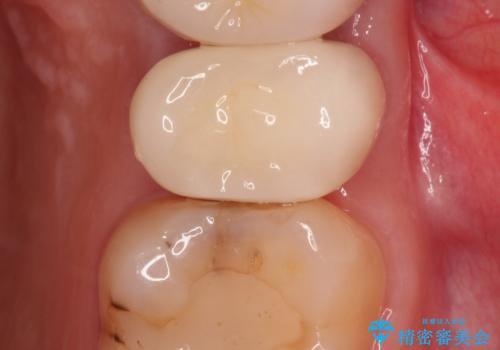

歯を部分矯正で引き上げて、虫歯を徹底的に取り除き、適合の良いかぶせ物を装着する計画としました。

虫歯にならないことも大事ですが、治療した歯の再治療が必要ないように、精密な治療をすることもとても重要です。